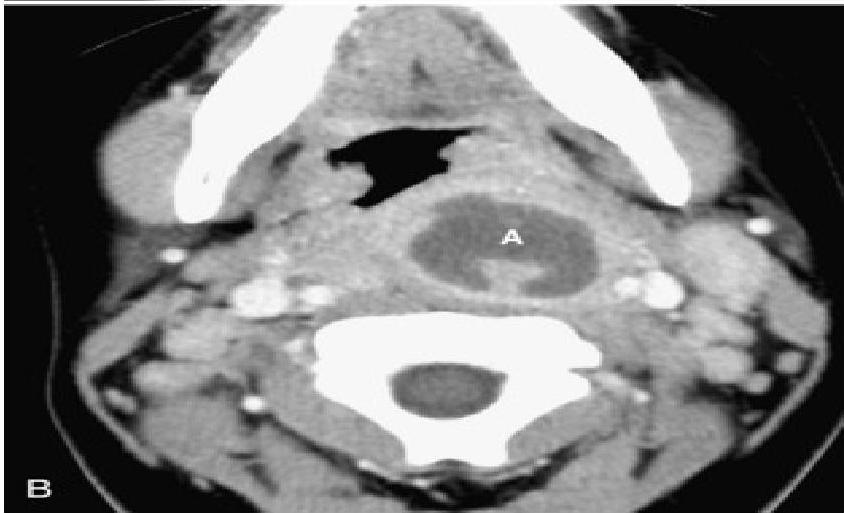

- Feature: An enlarged epiglottis protruding from the anterior wall of the hypopharynx (the “thumb sign”).

- Other findings: Thickened aryepiglottic folds, loss of vallecular air space, distended hypopharynx.

- Direct Visualization: Preferred if clinical suspicion is high. Performed during airway management in the operating suite. Shows a swollen, cherry-red epiglottis with an endotracheal tube passing posteriorly.